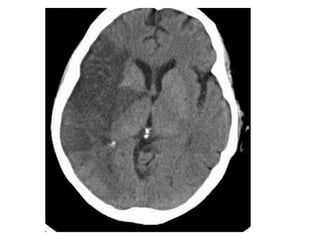

CT without contrast , cerebral venous thrombosis

CT without contrast , cerebral venous sinus thrombosis